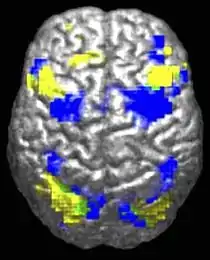

根據大腦是否正在做社會和非社會的任務,低功能自閉症相關的模式和在腦中的異常活化作用不同。有證據表明在自閉症缺省的腦網絡中減少功能連接,一個大規模的腦網絡參與社會和情感處理,具有完整的正面網絡連接,用在持續的關注和目標導向的思維方式。在自閉症患者的兩個腦網絡不能及時連接,這表明在兩個網絡之間切換的不平衡,這可能反映自我思想的干擾。

自閉症假說的連接理論,自閉症的特點是高層次的神經連接和同步的功能不夠,伴隨著過量的低級過程。對這一理論的證據在自閉症患者腦功能成像研究以及通過腦電波的研究,已經發現成人自閉症在皮質(cortex),局部過度連接,以及額葉之間和的其餘部分薄弱的功能聯繫。其它證據表明連接不夠主要是在每個大腦皮質半球內(hemisphere of the cortex),因此自閉症是皮質間聯繫的障礙。